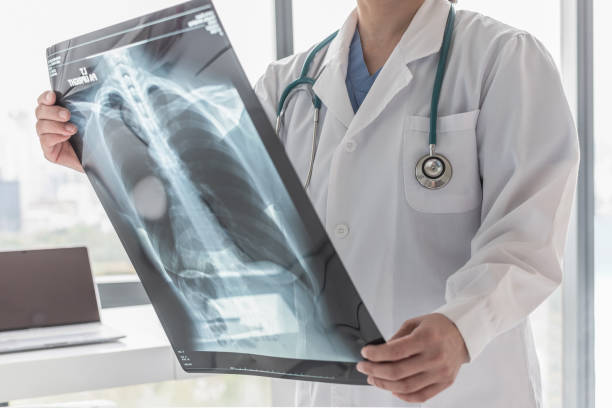

폐섬유화증은 폐조직 내 결손 및 염증에 의해 섬유화 과정이 일어나서, 건강한 폐조직이 염증과 섬유화에 대한 대체물질로 치환되는 질환입니다. 이로 인해, 섬유화된 조직은 신축성이 없고, 호흡기능이 저하됩니다. 따라서 다른 질병과 마찬가지로 초기에 적절한 치료를 받는 것이 중요하기 때문에 이번 시간에는 폐섬유화로 인한 증상들에 대해 정리해보겠습니다.